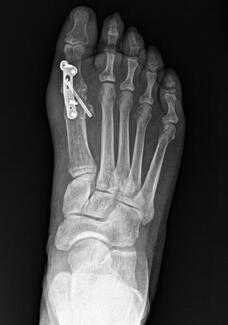

Figure 1. AP radiographs of the right foot fifth metatarsal. A: 1 day post-injury. B: 1 month. C: 4 months. D: 11 months.

Case Study

11/21/2025

Matthew Gorski, DPM; Christian Frey, DPM

This case demonstrates that isolated fifth metatarsal shaft fractures in healthy, active adults can potentially be managed conservatively with excellent outcomes.

Podiatry Today